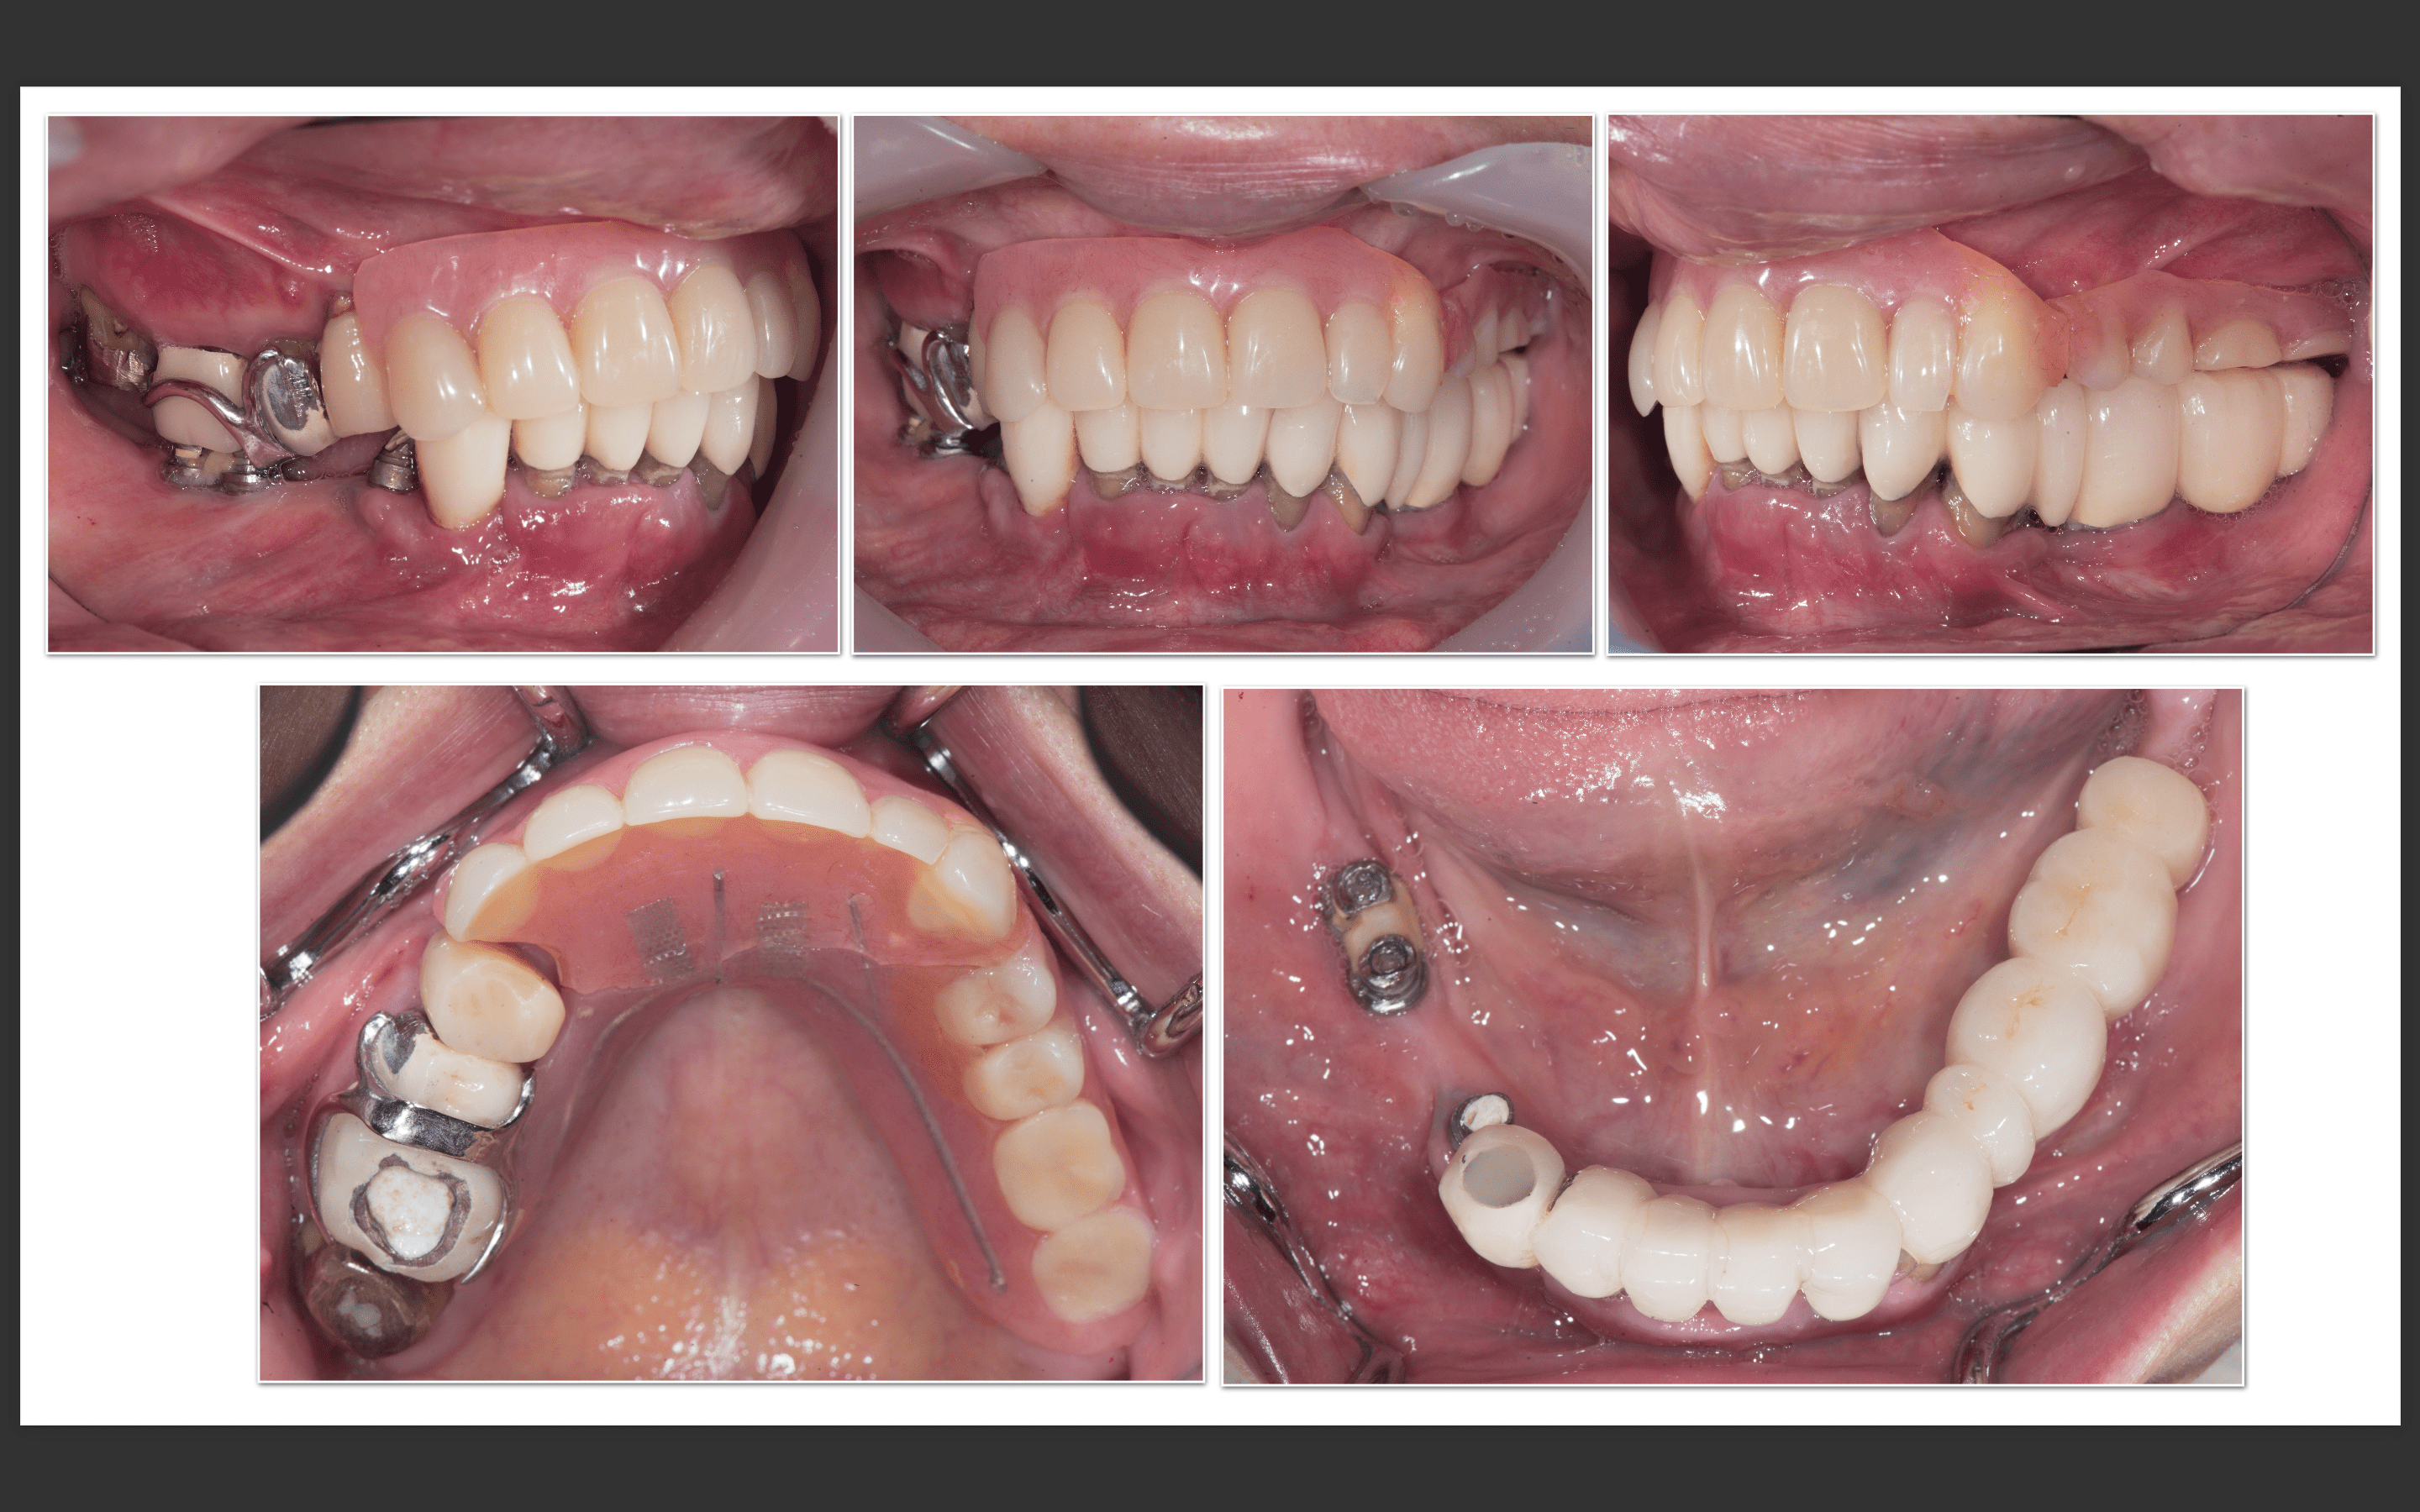

症例紹介28:オールオンシックス(All-on-6)インプラント治療《60代女性》

治療内容:現在他院で右上の根の治療をしているが、全体的に噛めないので治療を希望され来院。

上顎:虫歯がひどく、保存不可能な状態である。

下顎:インプラントが入っているが、被せ物がなずれたまま放置になっている。

上顎:根の病気と虫歯で保存不可のな状態。

下顎:インプラントが不適切な位置に入っており、撤去が必要な状態。

最終補綴

上顎:両側サイナスリフト後のロケーターアバットメントによる金属床ブリッジ

下顎:All-on-6によるフルジルコニアブリッジ

治療期間:約1年半

治療費:¥6,200,000(税込)

リスク:上顎のロケーターアバットは定期的に交換が必要です。また、上顎の人工歯が減ってきますので、定期的なメンテナンスが重要です。